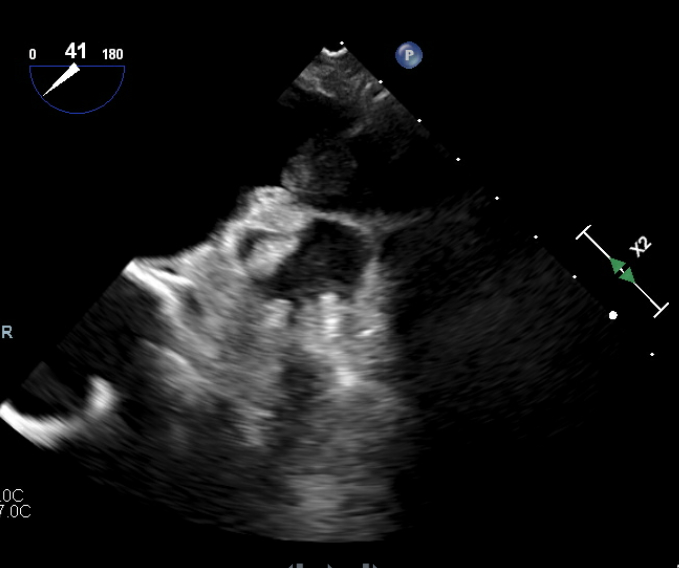

82-year-old male who presented with symptoms of progressively worsening shortness of breath and palpitations for 4 days. He was recently diagnosed with non-small cell carcinoma and underwent a left upper lobectomy a few months prior. Upon arrival, patient was tachycardic, with a heart rate in the 140s, requiring 5-6 L nasal cannula to maintain oxygen saturation above 92%. EKG revealed new onset atrial fibrillation with rapid ventricular response. Laboratory testing was remarkable for elevated NT-pro BNP to 4,000. CXR revealed bilateral pulmonary congestion consistent with pulmonary edema. Transthoracic echocardiogram was significant for severely reduced EF to 15-20%, previously normal. The patient was admitted for management of new onset-atrial fibrillation & HFrEF likely due to tachycardia-mediated cardiomyopathy. Cardioversion was initially planned; however transesophageal echocardiogram revealed an unexpected thrombus at the os of the left superior pulmonary vein. No thrombus was seen in the left atrial appendage. The patient was started on IV digoxin and low-dose esmolol drip for rate control along with a heparin drip for anticoagulation. However, the patient had sinus pauses for up to 5 seconds on esmolol drip. Given the limitation to control the heart rate, the patient underwent placement of CRT-P device. He was medically optimized and discharged with plan for outpatient cardioversion vs Atrial fibrillation ablation.

Atrial fibrillation with rapid ventricular response is a common precipitant of heart failure, often requiring rhythm control. The presence of intracardiac thrombus is a well-established contraindication due to the risk of systemic embolization. While most thrombi form in the left atrial appendage, our patient was found to have a thrombus in the left superior pulmonary vein, a unique and exceedingly rare finding. Most cases of pulmonary vein thrombosis are seen after catheter ablation, lobectomy, Lung transplantation, etc. Our case presented a unique dilemma due to the lack of guidelines addressing thromboembolic risk and cardioversion in this context. Therefore, a conservative approach was chosen with rate control and systemic anticoagulation. This case also highlights the value of comprehensive imaging like transesophageal echocardiography for through evaluation of pulmonary vein ostia in addition to left atrial appendage thrombus, especially in the context of recent thoracic surgery.